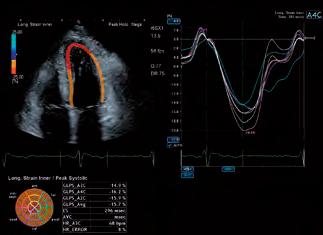

Research Partnership Buoyed by Canon Medical UK Investment

Knowledge of how the heart adapts to exercise and disease to be expanded by investment in research scholars and cardiac investigation techniques

Theaim of the Sports Cardiology & Research Partnership, a team of leading UK academics and medical institutions, is to advance the detection of serious cardiac disease. A new round of investment announced by Canon Medical Systems UK to appoint additional research scholars and expand echocardiography ultrasound and cardiac MRI investigation techniques will push its quest forward.

In the last year, the research team, comprising of experts from the University of Bristol, Bristol Heart Institute, the Children’s Health & Exercise Research Centre/University of Exeter (CHERC), and the Institute of Sport, Exercise and Health (ISEH) at University College London (UCL), has shaped international discussion on cardiac adaption in paediatric athletes, and exercise recommendations in children and

adults with congenital heart disease. This has been through the publication of scientific papers1, guidelines and participation in global conferences.

New studies are ongoing to quantitively assess the cardiac function during exercise of highly trained sports stars of the future. With Canon Medical UK’s support, the Sports Cardiology & Research Partnership has been able to generate one of the world’s largest datasets on the cardiovascular profile of young football players from the world’s leading football clubs and academies. Early data was presented to the 2021 International Olympic Committee World Conference on Prevention of Injury & Illness in Sport, while other research is currently under peer review with several leading journals.

“By understanding how the heart works in the highly trained athlete, we are able to apply these findings to those with congenital heart disease, with the aim of being able to detect potentially serious adverse outcomes earlier and promoting a healthy lifestyle to those with underlying heart disease,” states Dr Nathan Riding, Senior Research Associate at the Institute of Sport, Exercise and Health and Canon Medical UK

PRODUCT // ULTRASOUND // Research

Patient set-up for cardiopulmonary exercise testing in combination with an echocardiogram.

funded scholar. “Congenital heart disease affects approximately 1% of all live births but as surgeries are improved, and prognosis gets better, the number of children transitioning into adolescence and adulthood is increasing. By encouraging exercise adherence, our aim is to improve quality of life and life expectancy.”

Dr. Riding continues, “One hour of exercise per day is the recommended amount of activity time for a child without heart disease, yet just 23% of boys and 20% of girls aged 5 to 15 meet these targets. Children with congenital heart conditions are also failing to meet these activity guidelines, further impacted by a lack of formal exercise rehabilitation programmes which would be beneficial to them. At the opposite end of the spectrum, child athletes, especially those in sporting academies, may now be undertaking up to 16 hours per week of training, yet with unknown consequences on the heart. Our research is important for so many young people, from so many walks of life.”

Mark Hitchman, Managing Director of Canon Medical Systems UK states, “Unlocking knowledge from the

body through research is essential to evolve our understanding of how to improve mainstream health and wellbeing. Our increased investment in sports cardiology will not only benefit the sporting community, but also wider healthcare. We will be able to fine-tune our diagnostic imaging applications and health IT for cardiology and reshape procedures and protocols that can help improve people’s long-term outcomes.”

Institute of Sport, Exercise and Health at UCL, where the programme is led by Profs. Guido Pieles and Mathew Wilson, the mobile lab is able to look into heart health using the latest medical imaging and analysis tools to identify pre-existing cardiac conditions that may predispose an athlete to sudden cardiac death.

The Sports Cardiology & Research Partnership is led by Professor Guido Pieles, the team cardiologist for Manchester United, Prof Graham Stuart, a Football Association expert consultant cardiologist, and Prof Craig Williams, director of CHERC. The research centres at Bristol, Exeter and ISEH London are using state of the art echocardiographic equipment by Canon Medical Systems. //